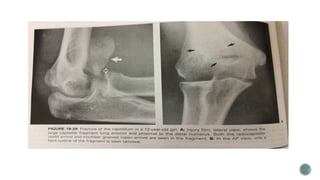

 Fracture involve only the true articular surface of lateral condyle

 Rarely seen in children

 Hahn – steinthal type – contains a rather large portion of cancellous bone of the lateral

condyle, lateral crista of trochlea is included

 Kocher – Lorenz is more of pure articular fracture with little if any subchondral bone